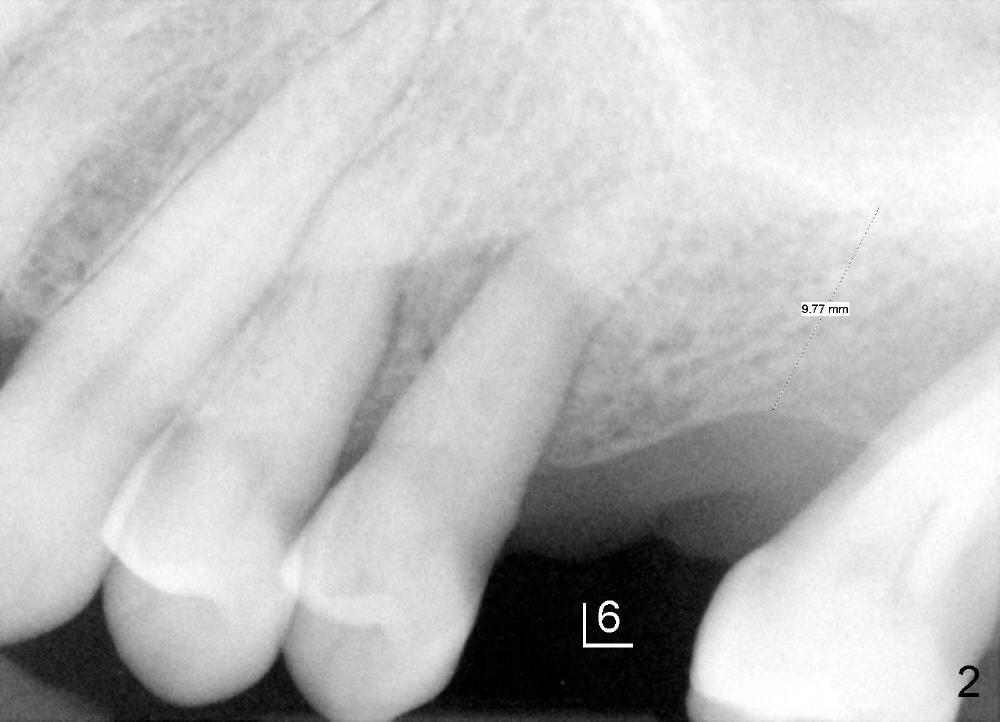

A 52-year-old man has periodontitis (Fig.1.2). The teeth #2 and 15 have been extracted (Fig.1 *). Those labeled as # have received root canal therapy.

He wants to have implant at the upper left 1st molar first. Fig.3 is a sagittal CT section of the edentulous area (4-5 years after Fig.1,2 was taken). It shows limited bone height (~ 3 mm) at the thinnest region, but it is thicker mesially (M) and distally (D): ~ 7 mm. Therefore a large implant (7 or 8 mm, Fig.5) can gain more bone height than a small one (5 mm, Fig.4). Trephine bur may be used to push the whole piece of bone upward (Fig.6). Trephine burs, osteotomes or bone expanders may be also used for sinus lift.